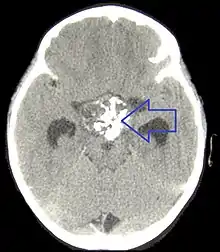

If one of these tests shows a deficiency of hormones produced by the pituitary, magnetic resonance imaging (MRI) scan of the pituitary is the first step in identifying an underlying cause. MRI may show various tumors and may assist in delineating other causes. Tumors smaller than 1 cm are referred to as microadenomas, and larger lesions are called macroadenomas.[1] Computed tomography with radiocontrast may be used if MRI is not available.[8] Formal visual field testing by perimetry is recommended, as this would show evidence of optic nerve compression by a tumor.[8]